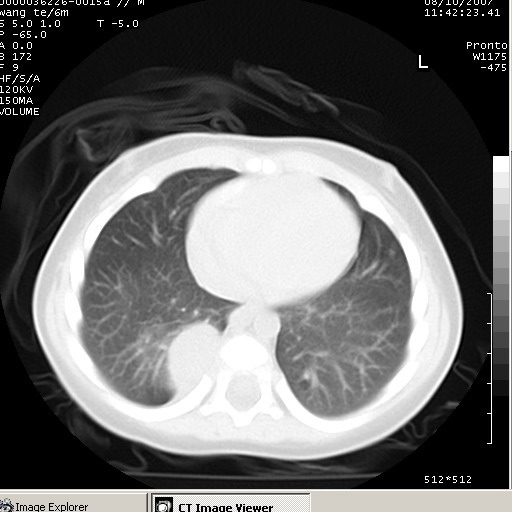

患儿男、6个月,因咳嗽三天曾拍胸片考虑肺部感染,这是在胸片后约一周左右作的ct。

右下肺纵隔旁软组织密度影,边界清楚,内见点状高密度影。支持考虑:神经源性肿瘤!

右下肺纵隔旁软组织密度影,宽基底紧贴胸椎与肋骨,边界清楚,内见点状高密度影。支持考虑:神经源性肿瘤!肺隔离症待排

右下肺纵隔旁软组织密度影,边界清楚,考虑神经源性肿瘤。

右下肺纵隔旁边界清楚软组织密度影,内见点状高密度影。考虑:神经源性肿瘤!

同意神经源性肿瘤的诊断,如果患儿一般情况不差的话,神经节细胞瘤可能性要大一些,隔离肺的可能性小,如果考虑叶内型隔离肺,孩子平时感染的机会可能比较多,增强后可排除

典型的神经源性肿瘤

支持神经源性肿瘤,有肋骨破坏。